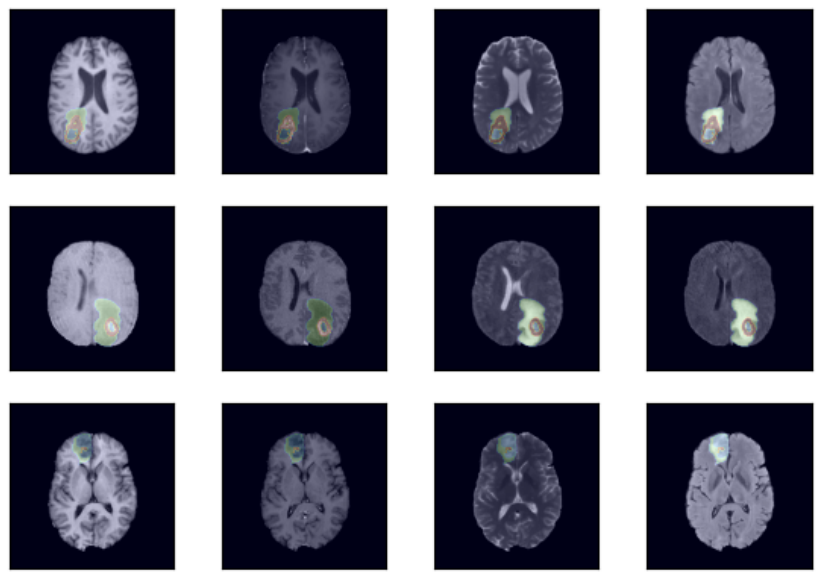

Semantic segmentation of brain tumors is a fundamental medical image analysis task involving multiple MRI imaging modalities that can assist clinicians in diagnosing the patient and successively studying the progression of the malignant entity. In recent y

따라서, Swin-Transformer 구조를 이용해서 작은 patch에서 큰 patch로 연산하는 과정을 통해서 segmentation이 더욱 세밀하고 best performance를 얻어내었다.